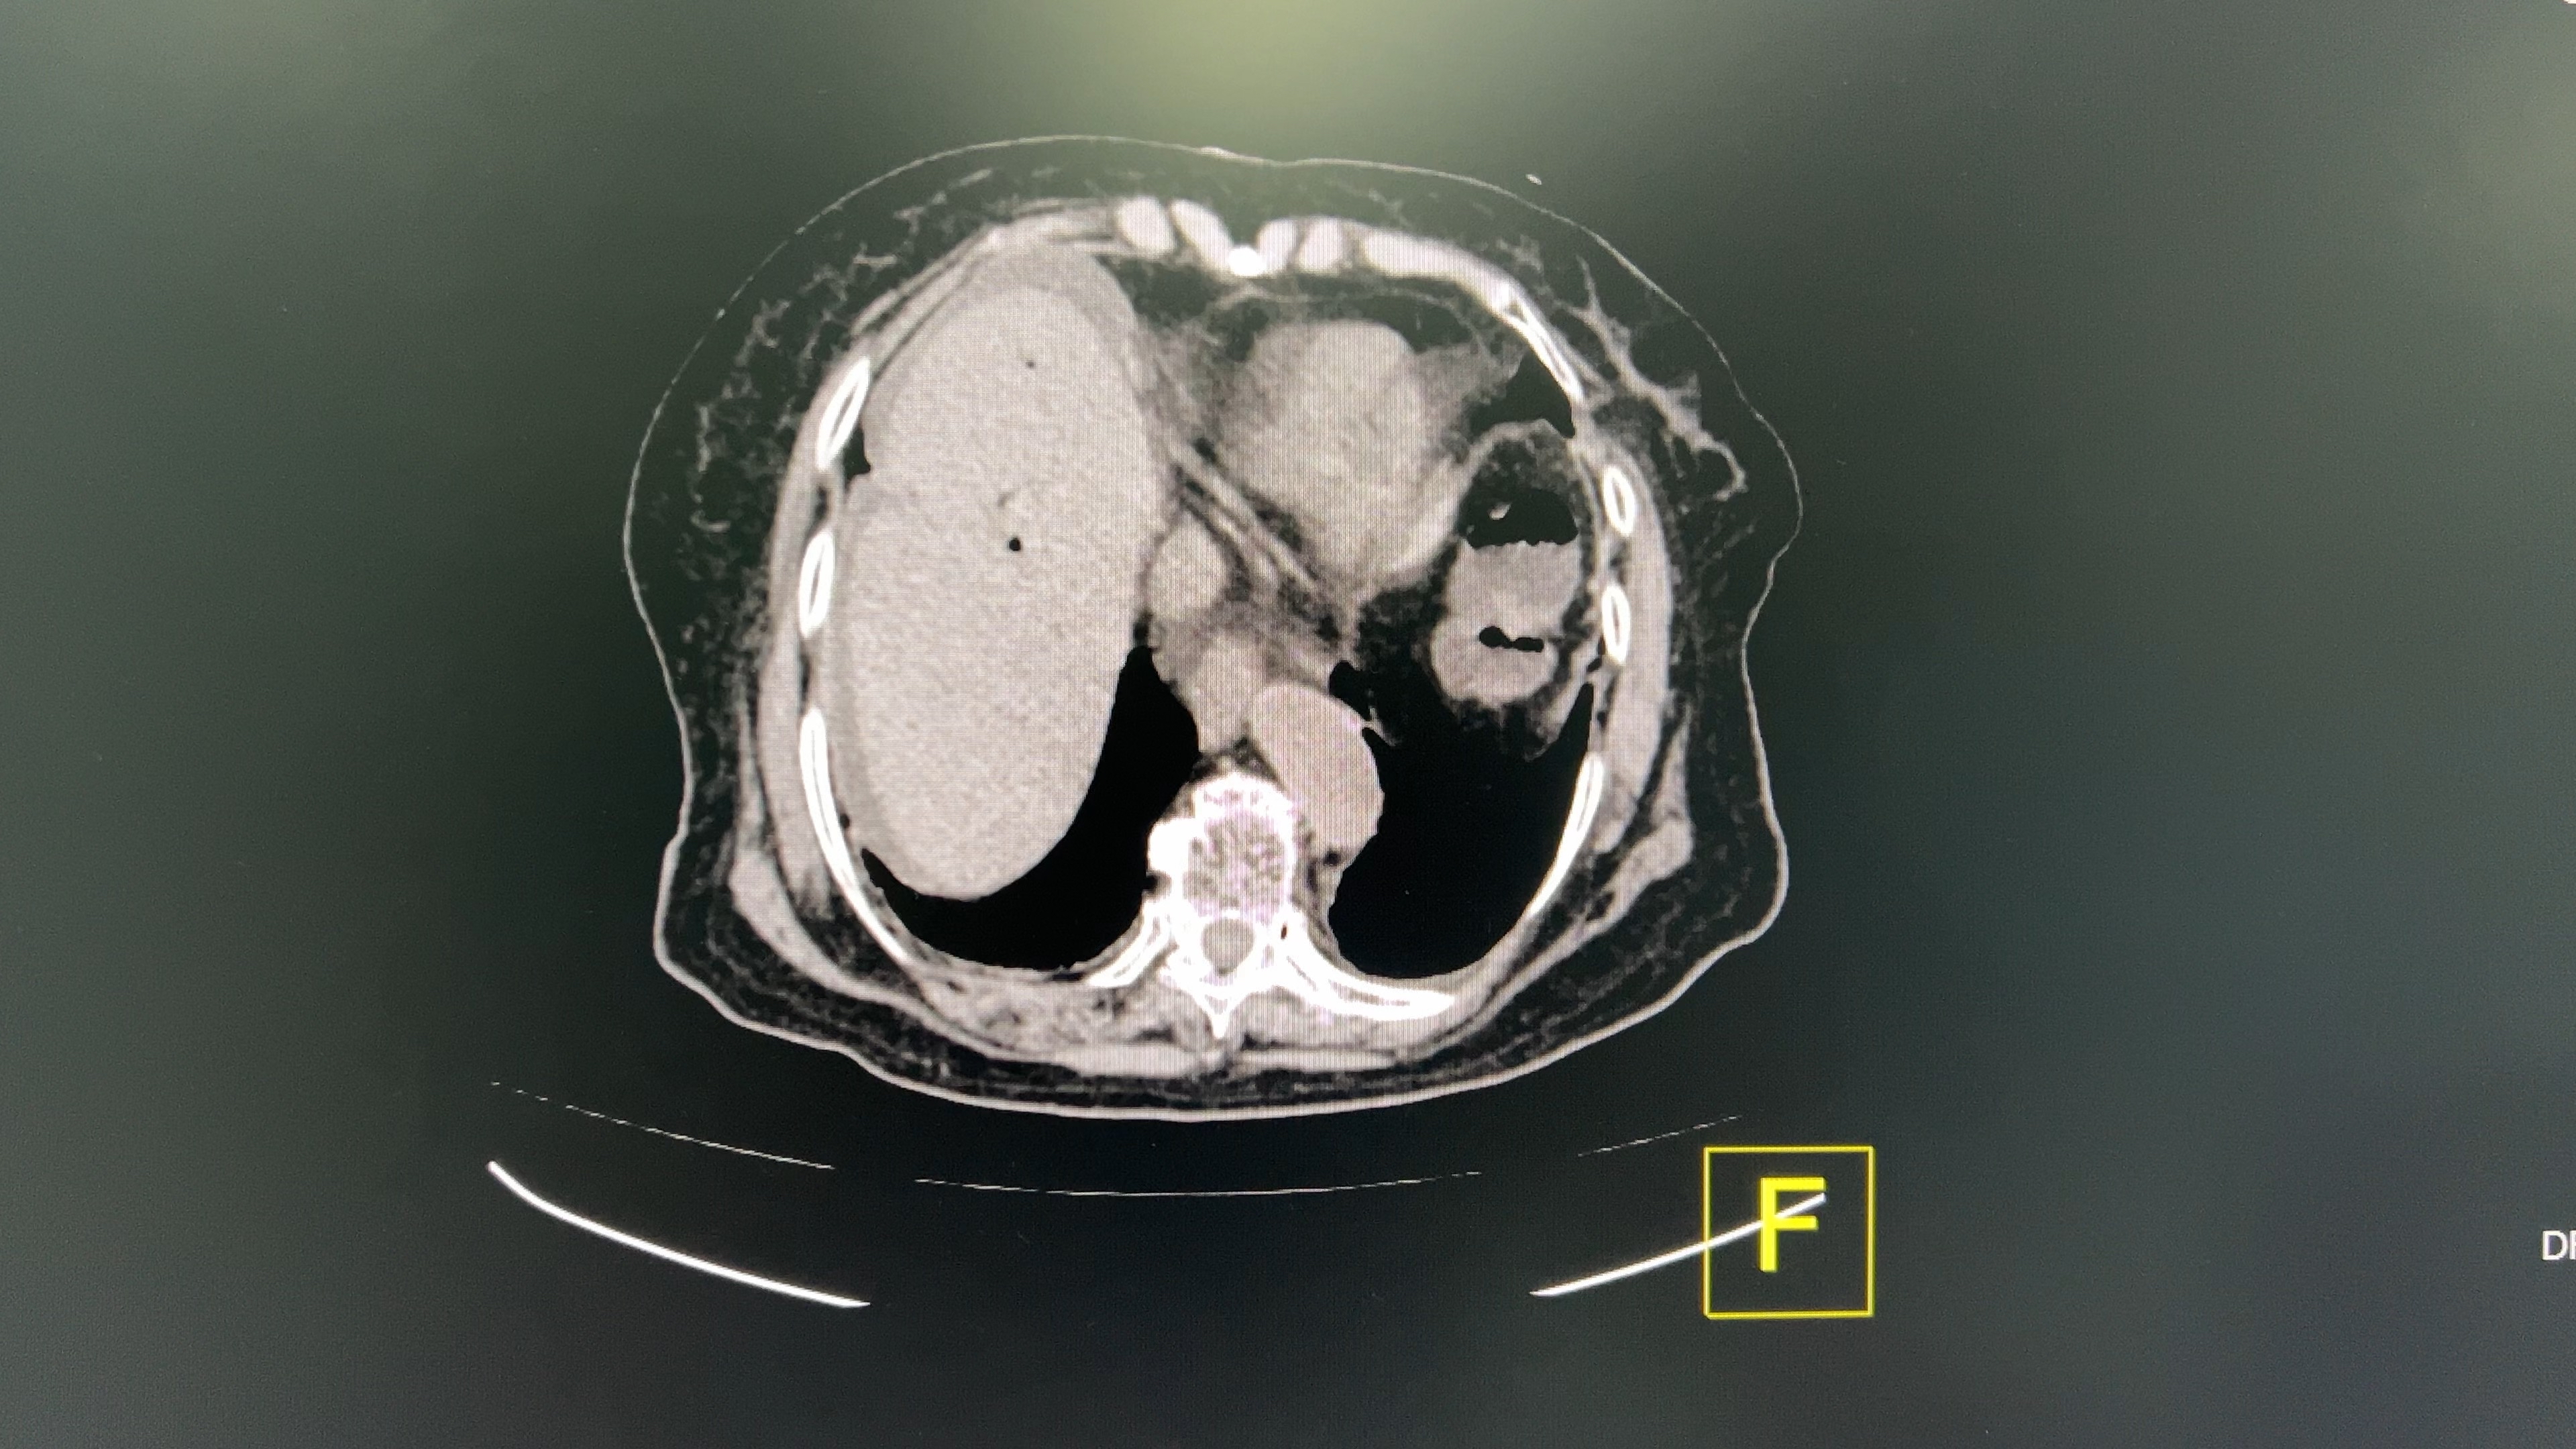

患者94岁老年女性,腹部胀痛伴呕吐2天入院,查体腹部彭隆,肚周压痛,伴有轻微反跳痛,院外腹部平片提示肠梗阻。

考虑什么诊断,该如何处理?